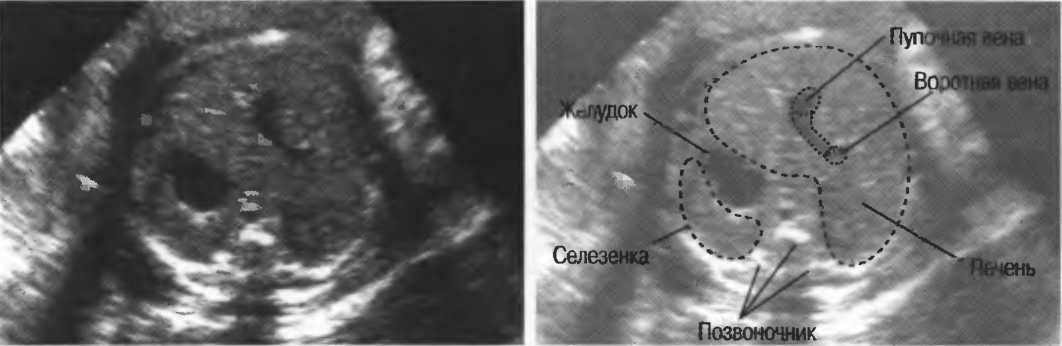

Рис.5. Два поперечных среза плода, демонстрирующих тень от позвоночника плода. Аналогичная тень от ребер может частично закрывать почки или печень. Изменяя угол наклона датчика, можно изменить положение тени таким образом, чтобы подлежащие ткани были видны отчетливо.

Череп плода, дифрагма, стенки сосудов, соединительная ткань являются примерами зеркальных отражателей (рис. 6).